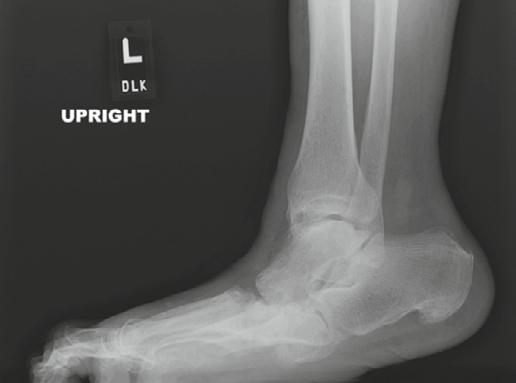

To illustrate the pitfalls of CN treatment, we have presented a 61-year-old male who already underwent midfoot fusion for prior Charcot event (Figure 2). He comes in for a second opinion and declined an ankle fusion and wanted to preserve his motion so that he could drive. The second set of radiographs demonstrate attempted hindfoot fusion that resulted in collapse to the talus bone in the ankle joint (Figure 3). Recent podiatric research shows an alternative treatment option to the traditional rigid fixation. The Charcot flipper foot construct involves fusing the hindfoot while leaving the midfoot mobile to allow for motion to lower risk of further breakdown (2). The final surgery was performed to replacing the dislocated talus with a cadaver bone and fusing the hindfoot with an intramedullary nail all through small incisions for preparation and hardware fixation. The

Figure 2. Initial presentation of 61-year-old male with new midfoot Charcot neuroarthropathy of the midfoot following previous midfoot surgery six-months previously. Collapse started after going to physical therapy (second Charcot event).